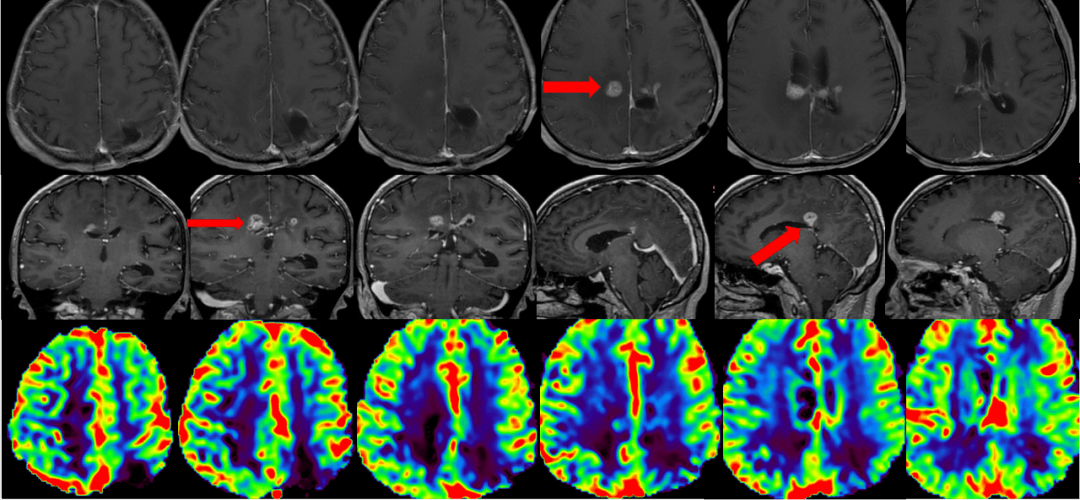

一例胶质母细胞瘤患者who4级术后tmz联合ttfields治疗总生存期16个月

爱见新生一例胶质母细胞瘤患者who4级术后辅助tmz联合肿瘤电场治疗总

爱见新生一例胶质母细胞瘤who4级idh野生型术后使用ttfields治疗总